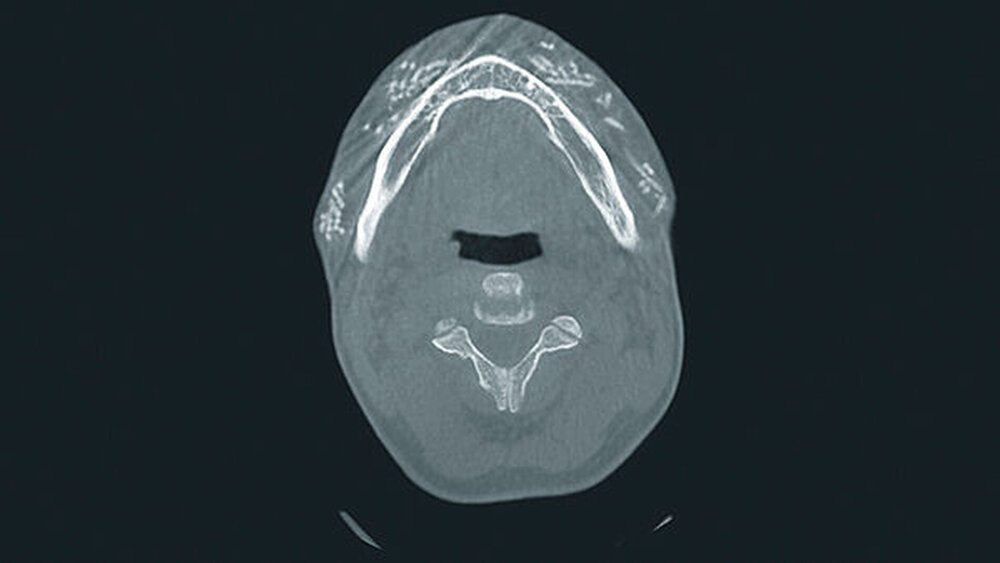

Zur Drainage wurden zwei Gummilaschen eingelegt. Bei weiter zunehmendem Druckschmerz im Bereich der V. angularis rechts erfolgte schließlich die stationäre Aufnahme zur i.v. antimikrobiellen und analgetischen Therapie, worunter es zu einer raschen Besserung kam. Eine im Rahmen des stationären Aufenthalts angefertigte digitale Volumentomografie zeigte etliche weitere Fremdkörper über den Gesichtsbereich verteilt (Abbildungen 2 bis 4).